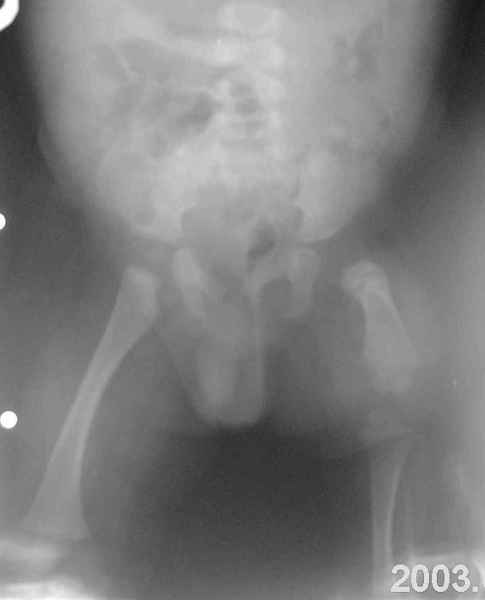

Извините за задержку(по техническим обстоятельствам) еще просим извинения за ошибки (трудный перевод). Больной с врожденной гипоплазией проксимальной части бедра, с ацетабулярной дисплазией. В 6 лет первая операция по стабилизации тазобедренного сустава прилагаю Рг. К нам обратился в следующей ситуацией:укорочение на 26см нижней конечности, соха flecta - 45 °.подвижной до 100°, genu flexum 25-30° мобильный до 90°. Активность мышц бедра- очень слабое, мышцы голени и сама голень отстающей в развитии. В настоящее время пациент ходит самостоятельно с протезом. Спасибо всем еще раз за присланные варианты лечения.Rx при рождении:ниже

Rx на сегодняшнии день